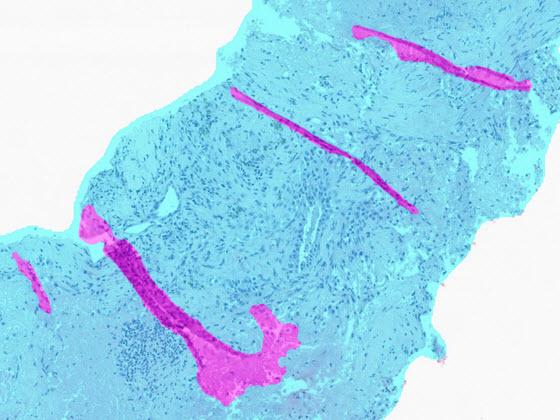

After selecting an image, view the H&E or IHC slide in the viewer and the SlideQC BF results. Results include overlays and quantitative results. The overlay highlights artifacts in magenta and acceptable tissue areas in cyan.

Use the quantitative SlideQC BF results to automatically tag images exceeding a laboratory-defined artifact threshold for recut or rescan. These images can be triaged into separate worklists for additional work.